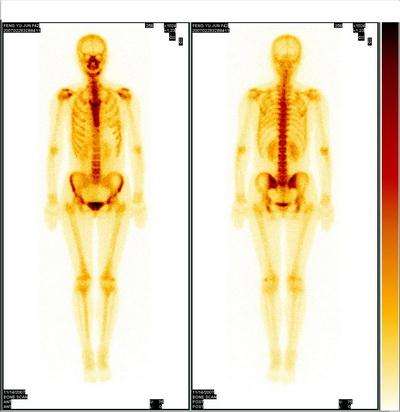

一位男性患者前列腺癌手术后2年多,疾病控制得很好,没有复发迹象。一天,他突然出现会阴部疼痛,入院检查发现骶骨及尾骨转移,于是患者接受了骨转移的姑息性放射治疗,还进行了双磷酸盐的骨修复治疗,局部未再出现疼痛。

1年后,对侧坐骨又出现了疼痛,“有经验”的患者直接来到了医院放疗科就诊,经过医生仔细地检查评估以后,上次放射治疗过的病灶已经部分愈合,这次疼痛的部位出现了新的病灶,但仍然局限。于是,放疗科医生仔细地给他设计了放疗方案,既保证了新病灶的治疗,又确保曾经接受过治疗的周边正常组织不会超出耐受剂量量引起不良作用。2周以后,疼痛缓解。患者再去接受了新一轮的内分泌治疗,不用挨痛,回家休养了。

除了需要手术的骨转移灶,其它部位的骨转移病灶出现疼痛,都可以通过放疗来止痛,疗程可以从1天到4周不等,局部治疗的疼痛缓解率可以达80%~90%。而且,如果在放疗病灶以外,有新发的骨转移病灶,仍然可以通过放疗来缓解疼痛。

有70%左右的骨转移会导致溶骨性骨折,经放疗后骨头会再愈合(再骨化作用)。